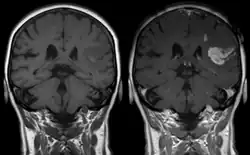

Magnetic resonance imaging

Gadolinium-based pharmaceuticals alter the relaxation time, and hence spectral line shape, of those protons that are in water molecules that are transiently attached to the paramagnetic atoms, resulting contrast enhancement of the MRI image.[11] This allows better visualisation of some brain tumours.[11]